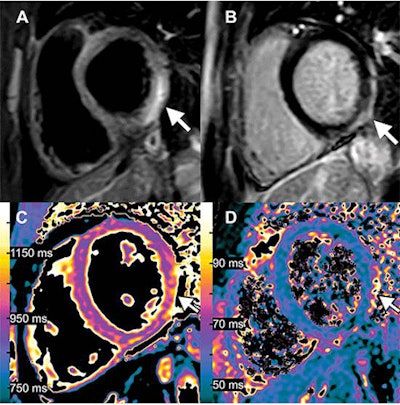

Images of a 15-year-old boy with myocarditis after COVID-19 vaccination. One day after receiving his second vaccination dose, he developed fever, myalgia, and intermittent tachycardia. (A) T2-weighted short inversion time inversion recovery MRI scan at 1.5 T in short-axis view shows focal high-signal intensities (arrow) at basal lateral and inferior wall, indicating myocardial edema. (B) Late gadolinium enhancement image in short-axis view shows corresponding linear subepicardial enhancement (arrow), indicating inflammatory myocardial necrosis. (C) T1 mapping and (D) T2 mapping in short-axis view show elevated T1 and T2 at the mid ventricular lateral and inferolateral wall (arrow in C and D), indicating acute myocardial injury (focal T1, 1165 msec; focal T2, 70 msec; institution-specific cutoff values for acute myocarditis: T1 global ≥1000 msec, T2 global ≥55.9 msec). Image courtesy of Radiology.The second runner-up was a tie between two articles. The first, "CT of Ongoing Intracerebral Hemorrhage," is by a group at the People's Hospital of Deyang City in Sichuan, China. The image captured the rapid evolution of a progressively expanding intracerebral hemorrhage in a 73-year-old man.